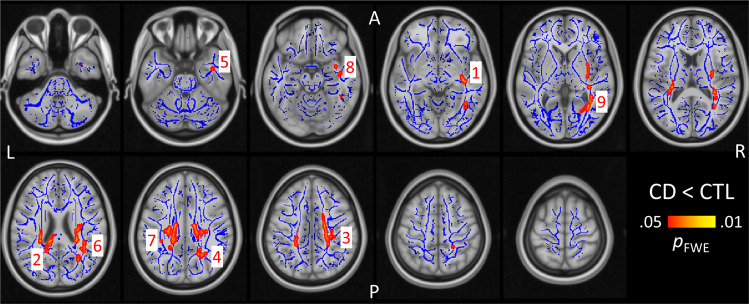

We compared whether white matter integrity, as indexed by fractional anisotropy, differed between CD and CTL along the white matter skeleton. Two-sample t tests revealed nine significant clusters where CD showed significantly lower fractional anisotropy than CTL (pFWE < 0.05; Fig. 1; Table 1). These clusters included a right-lateralized set of tracts innervating the external capsule, posterior corpus callosum, inferior temporal cortex, posterior thalamic radiation, as well as bilateral superior longitudinal fasciculus. Among the CD group, fractional anisotropy did not correlate with tobacco usage in any cluster, even when uncorrected (|r|’s < 0.20, p’s > 0.05).

Table 1: Two-sample t test results showing regions with significantly lower fractional anisotropy in the CD group relative to controls

| Sagittal striatum/external capsule R | 1 | 1730 | 0.04 | 35 | −15 | −10 |

| Splenium of corpus callosum | 2 | 1418 | 0.033 | −15 | −34 | 27 |

| Superior corona radiata R | 3 | 356 | 0.047 | 21 | −26 | 44 |

| Posterior corona radiata R | 4 | 331 | 0.044 | 25 | −59 | 28 |

| Inferior temporal R | 5 | 119 | 0.048 | 39 | −2 | −35 |

| Superior longitudinal fasciculus R | 6 | 111 | 0.049 | 38 | −48 | 20 |

| Superior longitudinal fasciculus L | 7 | 49 | 0.048 | −33 | −33 | 36 |

| Uncinate fasciculus R | 8 | 31 | 0.049 | 36 | −1 | −20 |

| Posterior thalamic radiation R | 9 | 3 | 0.05 | 29 | −52 | 0 |

There were no significant results for the reverse contrast, i.e. CD > CTL. “Cluster number” refers to the labels provided in Fig. 1

MNI Montreal Neurological Institute, R right, L left